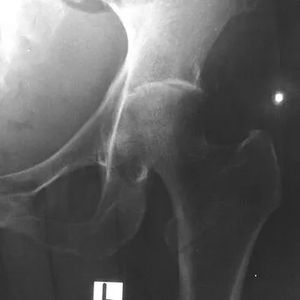

평균 잠복기는 9일(범위 1~21일)이다.[1] 거의 익사한 경우에는 24시간 내에 증상이 나타날 수 있다.[43] 발열, 기침, 근육통 등 감기와 유사한 증상이 나타나며, 폐렴, 패혈증, 농양 등 심각한 증상으로 진행될 수 있다. 간, 비장, 폐, 전립선, 신장 등 다양한 장기에 영향을 미치며, 뇌척수염, 뇌 농양, 급성 신우신염, 패혈성 관절염, 골수염 등 심각한 합병증을 유발할 수 있다.[1]

감염 경과에 따라 다른 심각한 증상이 발생한다. 감염된 사람의 약 1~5%가 뇌척수염 또는 뇌 농양을 앓고, 14~28%는 급성 신우신염, 신장 농양 또는 전립선 농양을 앓고, 0~30%는 목 또는 이하선 농양을 앓고, 10~33%는 간, 비장 또는 장 주위 농양을 앓고, 4~14%는 패혈성 관절염 및 골수염을 앓는다.[1]

흉부 X선 촬영에서는 다양한 결절 병변, 융합되는 결절, 공동 등이 나타날 수 있다. CT 스캔은 간 농양에서 특징적인 "벌집 징후"를 보여주며, 뇌 유비저의 경우 MRI가 CT보다 병변 진단에 더 유용하다.[7]

흉부 X-ray는 다발성 결절 병변이나 융합되는 결절, 공동을 보여줄 수 있다. 혈류 확산이 없는 급성 유비저의 경우, 흉부 X-ray는 상엽 경결 또는 공동을 보여준다.[7] 만성 유비저에서는 폐의 상엽 경결이 서서히 진행되어 결핵과 유사하다.[7] 폐 이외의 간과 비장 농양의 경우, CT 스캔이 초음파 스캔보다 더 민감하다. CT 스캔은 간 농양에서 "벌집 징후"(얇은 중격으로 분리된 격실이 있는 농양)를 보여준다.[7] 뇌를 침범하는 유비저의 경우, MRI가 CT 스캔보다 병변 진단에 더 민감하며, 고리 강화 병변을 보여준다.[7]6. 예방

당뇨병, 만성 신장 질환, 암과 같은 기저 질환은 감염에서 회복된 환자의 장기 생존과 장애를 악화시킬 수 있다. 유비저의 합병증 중 하나는 뇌척수염이다. 이는 사지마비(모든 사지의 근력 약화), 부분적 이완성 하지 마비(두 다리의 근력 약화), 또는 족하수를 유발할 수 있다. 과거 유비저 관련 뼈 및 관절 감염이 있었던 환자의 경우, 누관 감염, 제한된 운동 범위의 뼈 및 관절 변형과 같은 합병증이 발생할 수 있다.[1] 폐렴이나 패혈증을 일으키기도 하며 패혈증 상태에서의 치사율은 50% - 90%로 매우 높다.[107]